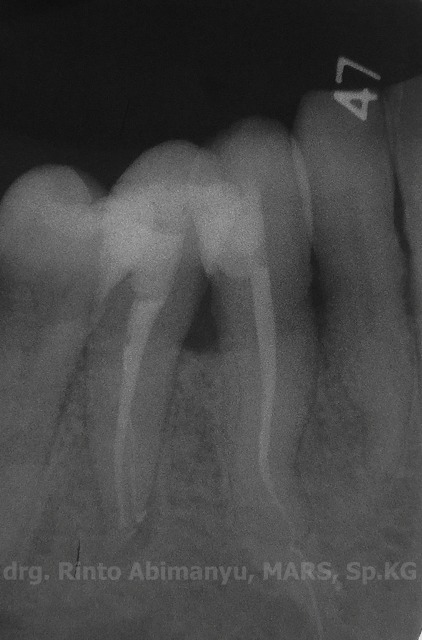

Radiografis gigi 43

Wah saluran akarnya agak “meliuk’ nih hehehe… Saya suka deg2an kalau mendapatkan saluran yang seperti ini, karena pengerjaannya harus hati2 dan sabar…